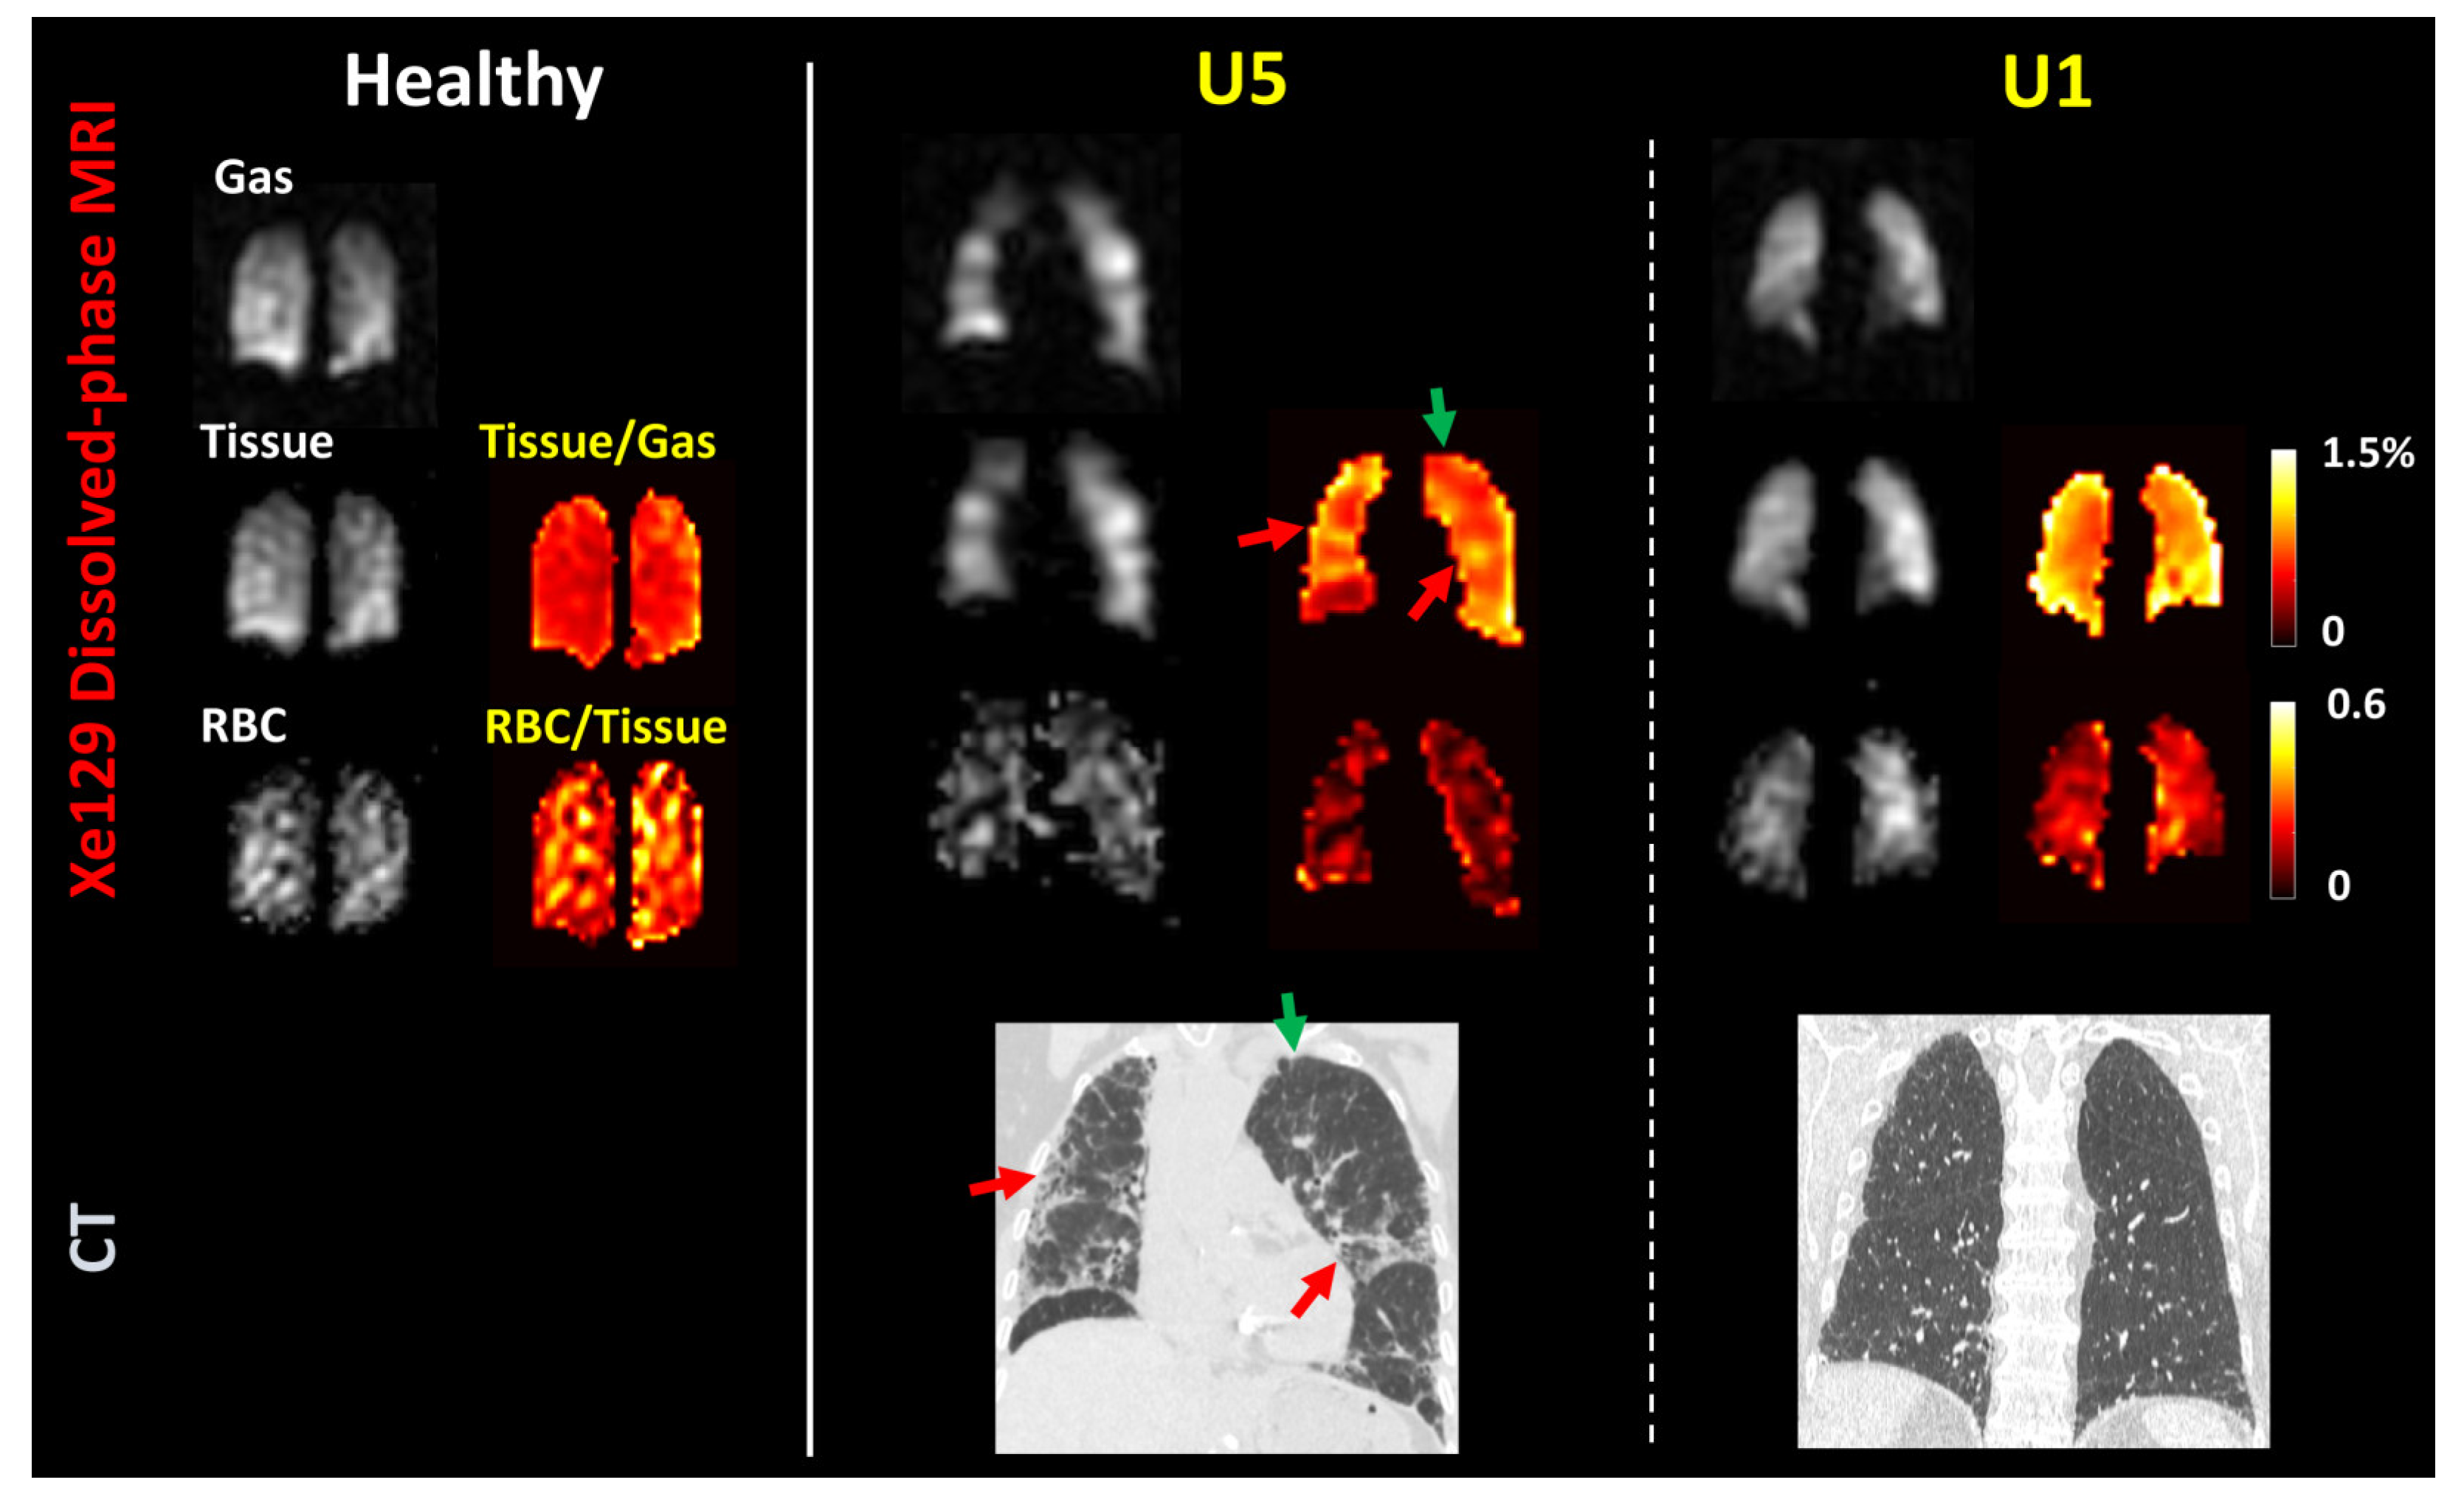

3.3. Measures from Dissolved-Phase 129Xe MRI and Comparison with CT

| Tissue-to-gas ratio | 1.0 (0.97–1.2) | 1.4 (1.3–1.6) | 0.014 | |

| RBC-to-tissue ratio | 0.27 (0.22–0.28) | 0.20 (0.18–0.23) | 0.004 |